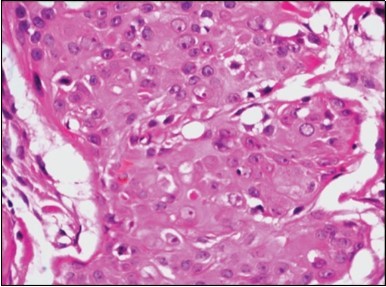

Granular arrangement of malignant cells and intercellular bridges are conspicuous with the demonstration of nuclear atypia, pleomorphism, prominent mitosis and tumour necrosis. A peripheral palisade is discernible within the cellular aggregates. Mitotic figures are common and can be quantified as up to 12 mitosis/ high power field. Tumour differentiation can prominently be of the ductal category with the demonstration of intra-cytoplasmic lumina. Comedo type tumour necrosis is evident along with foci of squamous differentiation The neoplasm is reactive to periodic acid Schiff ‘s (PAS) stain. (Figure 1, Figure 2, Figure 3, Figure 4, Figure 5, Figure 6, Figure 7, Figure 8, Figure 9, Figure 10, Figure 11, Figure 12, Figure 13.

Figure 4.Cellular atypia, mitosis and focal necrosis in eccrine porocarcinoma(16).

Figure 7.Aberrant and malignant epithelium with cellular proliferation and pleomorphism in eccrine porocarcinoma with frequent mitosis(19).

Figure 8.Disseminated atypical epithelial cells with cellular and nuclear pleomorphism, hyperchromasia, indistinct cytoplasm, vesicular nucleoli and central keratinization in eccrine porocarcinoma(20).